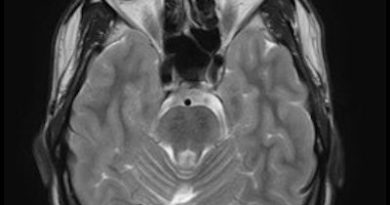

31 yaş, K, adölesan dönemde başlayan myoklonik nöbet

Güncel mikst tip nöbet

Closed lip schizencephaly

(Kapalı dudak) şizensefali

Closed lip şizensefali ve kortikal kalınlaşma-polimikrogiri

Closed lip şizensefali- polimikrogri